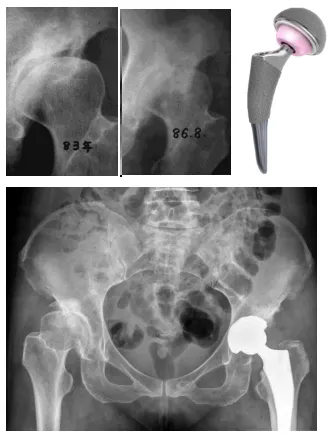

(35歲患者診斷DDH后未及時(shí)矯正,3年發(fā)展為髖骨關(guān)節(jié)炎行全髖關(guān)節(jié)置換術(shù))

雖然目前的人工全髖關(guān)節(jié)置換手術(shù)已經(jīng)非常成熟,效果滿意,但是仍然存在人工關(guān)節(jié)假體使用壽命年限的問(wèn)題,而且也存在感染和脫位等并發(fā)癥。尤其是年輕人,還不得不面對(duì)人工關(guān)節(jié)使用年限到了之后再次翻修的問(wèn)題。因此如何避免早期DDH患者發(fā)展為髖骨關(guān)節(jié)炎,成為了關(guān)節(jié)外科醫(yī)生不得不面對(duì)的事情。